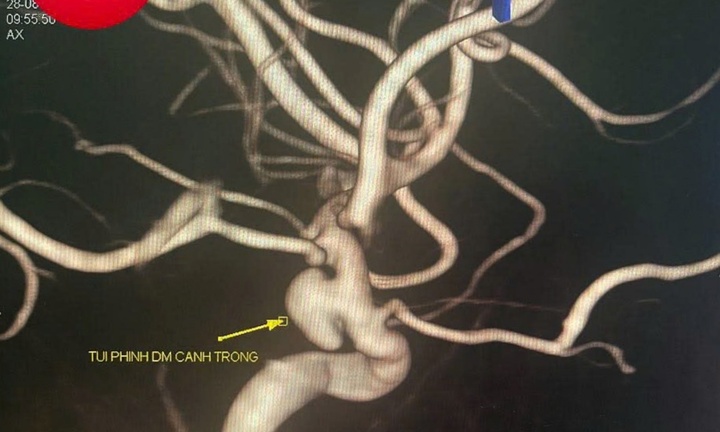

Đặc biệt, người có bệnh mạch vành tiềm ẩn, vận động quá sức có thể làm bong tróc mảng xơ vữa, gây tắc nghẽn mạch máu dẫn đến đột quỵ hoặc nhồi máu cơ tim. Các bài tập ép ngực, nín thở nâng tạ nặng (Valsalva) hoặc dùng chất kích thích càng làm tăng nguy cơ này.

Nhiều người trẻ cho rằng sức khỏe tốt thì không cần khám tim mạch. Tuy nhiên, một số rối loạn nhịp nguy hiểm như hội chứng Brugada, QT dài bẩm sinh, bệnh cơ tim giãn có thể không có triệu chứng rõ ràng cho đến khi xảy ra biến cố. Việc kiểm tra tim mạch định kỳ, đặc biệt là điện tâm đồ, siêu âm tim hoặc test gắng sức, là cần thiết trước khi bắt đầu tập luyện cường độ cao để phát hiện sớm các bệnh lý tiềm ẩn.